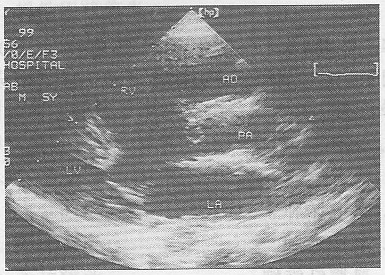

5.患者,男,30歲,常感心悸、氣促,超聲檢查如圖所示,該病例最可能的診斷是

正確答案:B 解題思路:室間隔與左室后壁非對稱性肥厚。